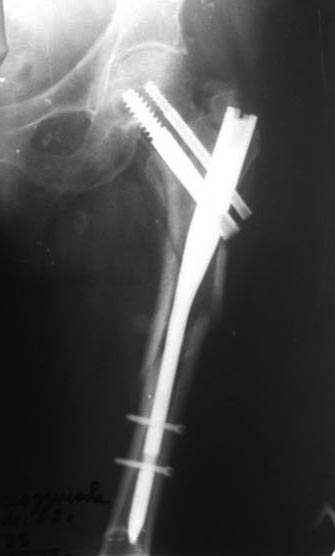

Перелом PFN

Добрый день, уважаемые коллеги. Пациентка Т. 79 лет травма 11 мес. После операции передвигалась при помощи костылей с дозированной нагрузкой.

Со слов, через месяц после операции появилась боль в области перелома, за мед помощи не обращалась. Сопутствующая патология бронхиальная астма ( на гормонах)

Хорошая иллюстрация того, что стандартную версию PFN нельзя использовать при локализации перелома ниже уровня малого вертела.

Нужно было гвоздь для диафизарных переломов ставить. Медиальной опоры нет, гвоздь короткий, перегрузка по каналу для винта и закономерный перелом импланта.

Гвоздь толщиной 10 мах 11 мм, и длинная версия тоже сломалась бы. Длинный согласен, но добавляю толстый с рассверливанием , и с фиксацией в шейку.Учитывыя возраст пациентки, длину гвоздя можно взять за вычетом дистального отломка, который пробить до метафиза и оставить там не усложняя операцию его удалением ( похоже он не канюлированный и это может быть проблемой)